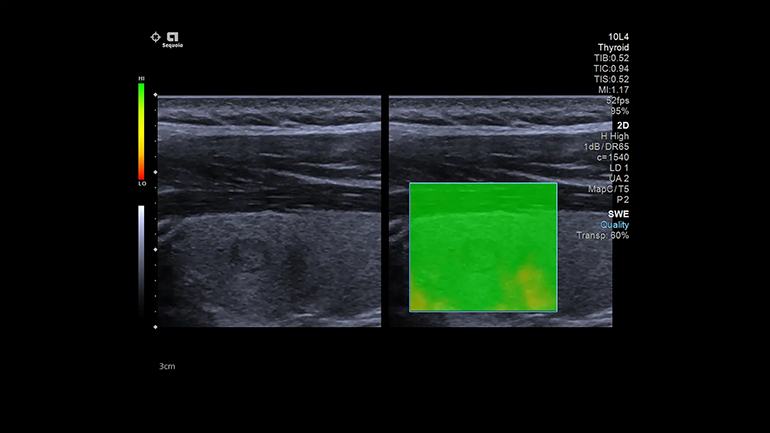

Графические изображения результатов. Карты качества

Карты качества позволяет немедленно оценить качество сдвиговых волн и повысить достоверность диагностики.